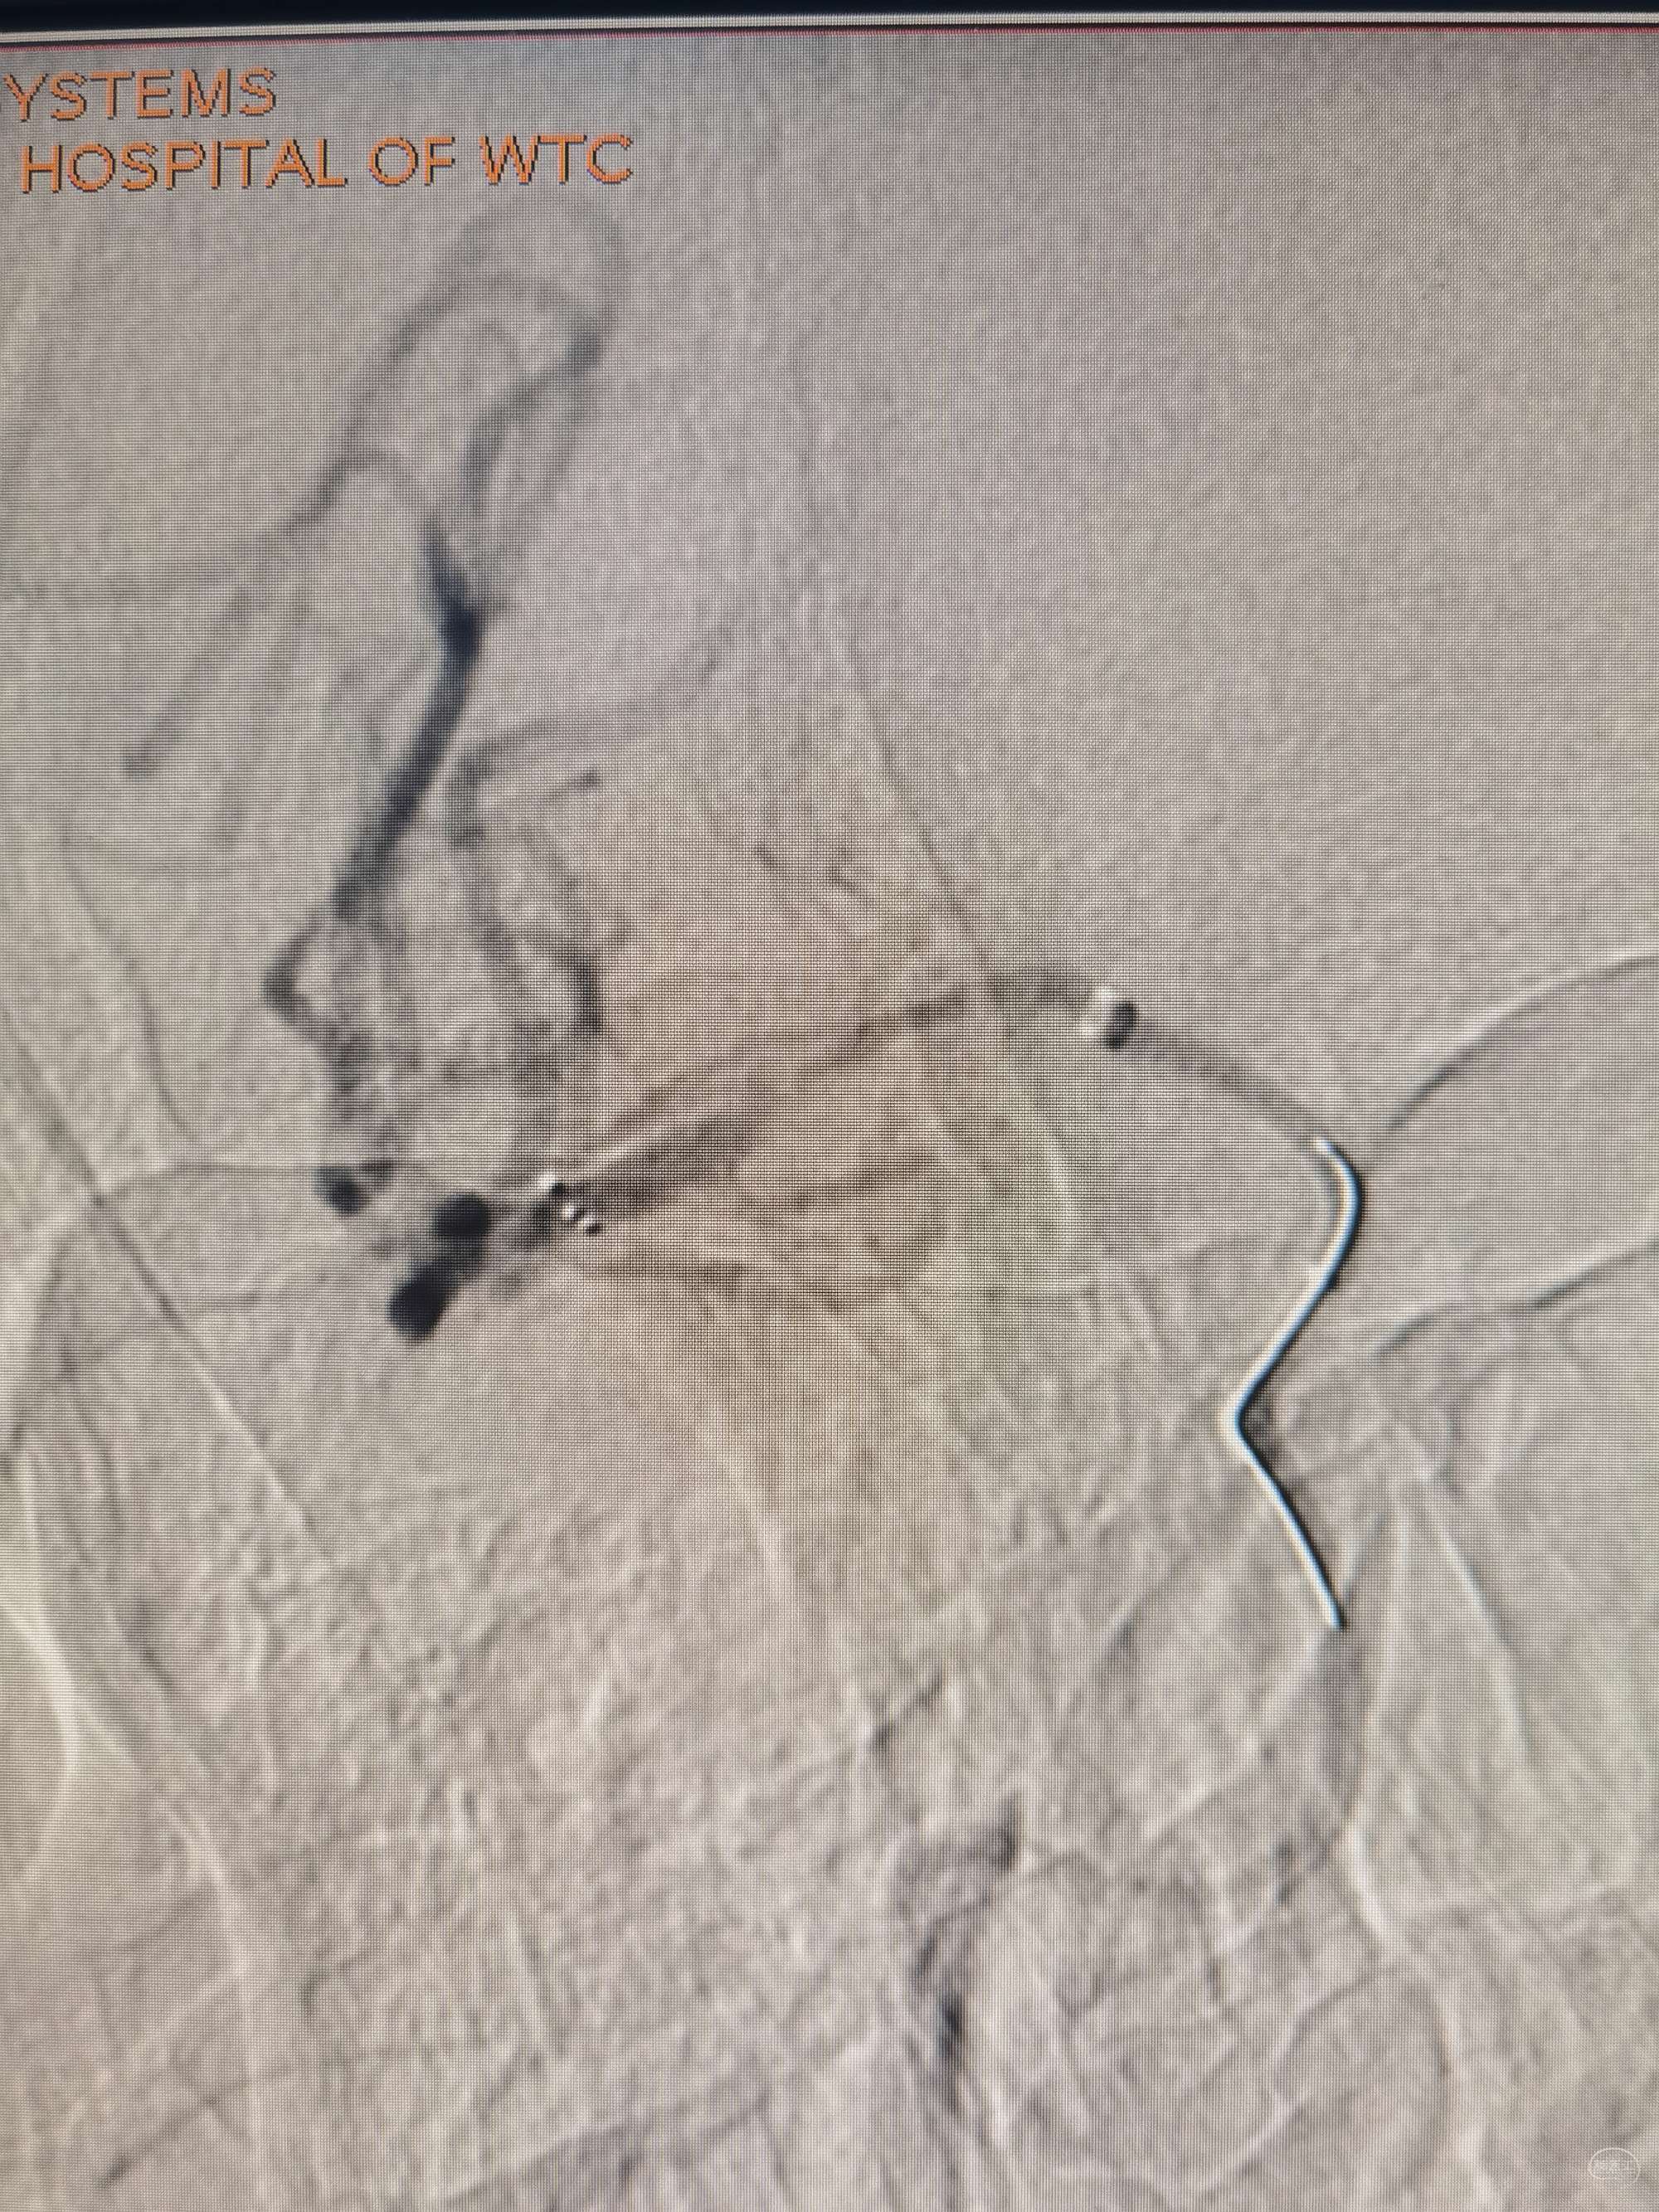

双微通过病变部位

4*20取栓支架释放后极轻手推造影

支架也放了还是取一把,取出小栓子1枚,再次造影:m1远端重度狭窄,微导丝再次通过后即可见远端血流差